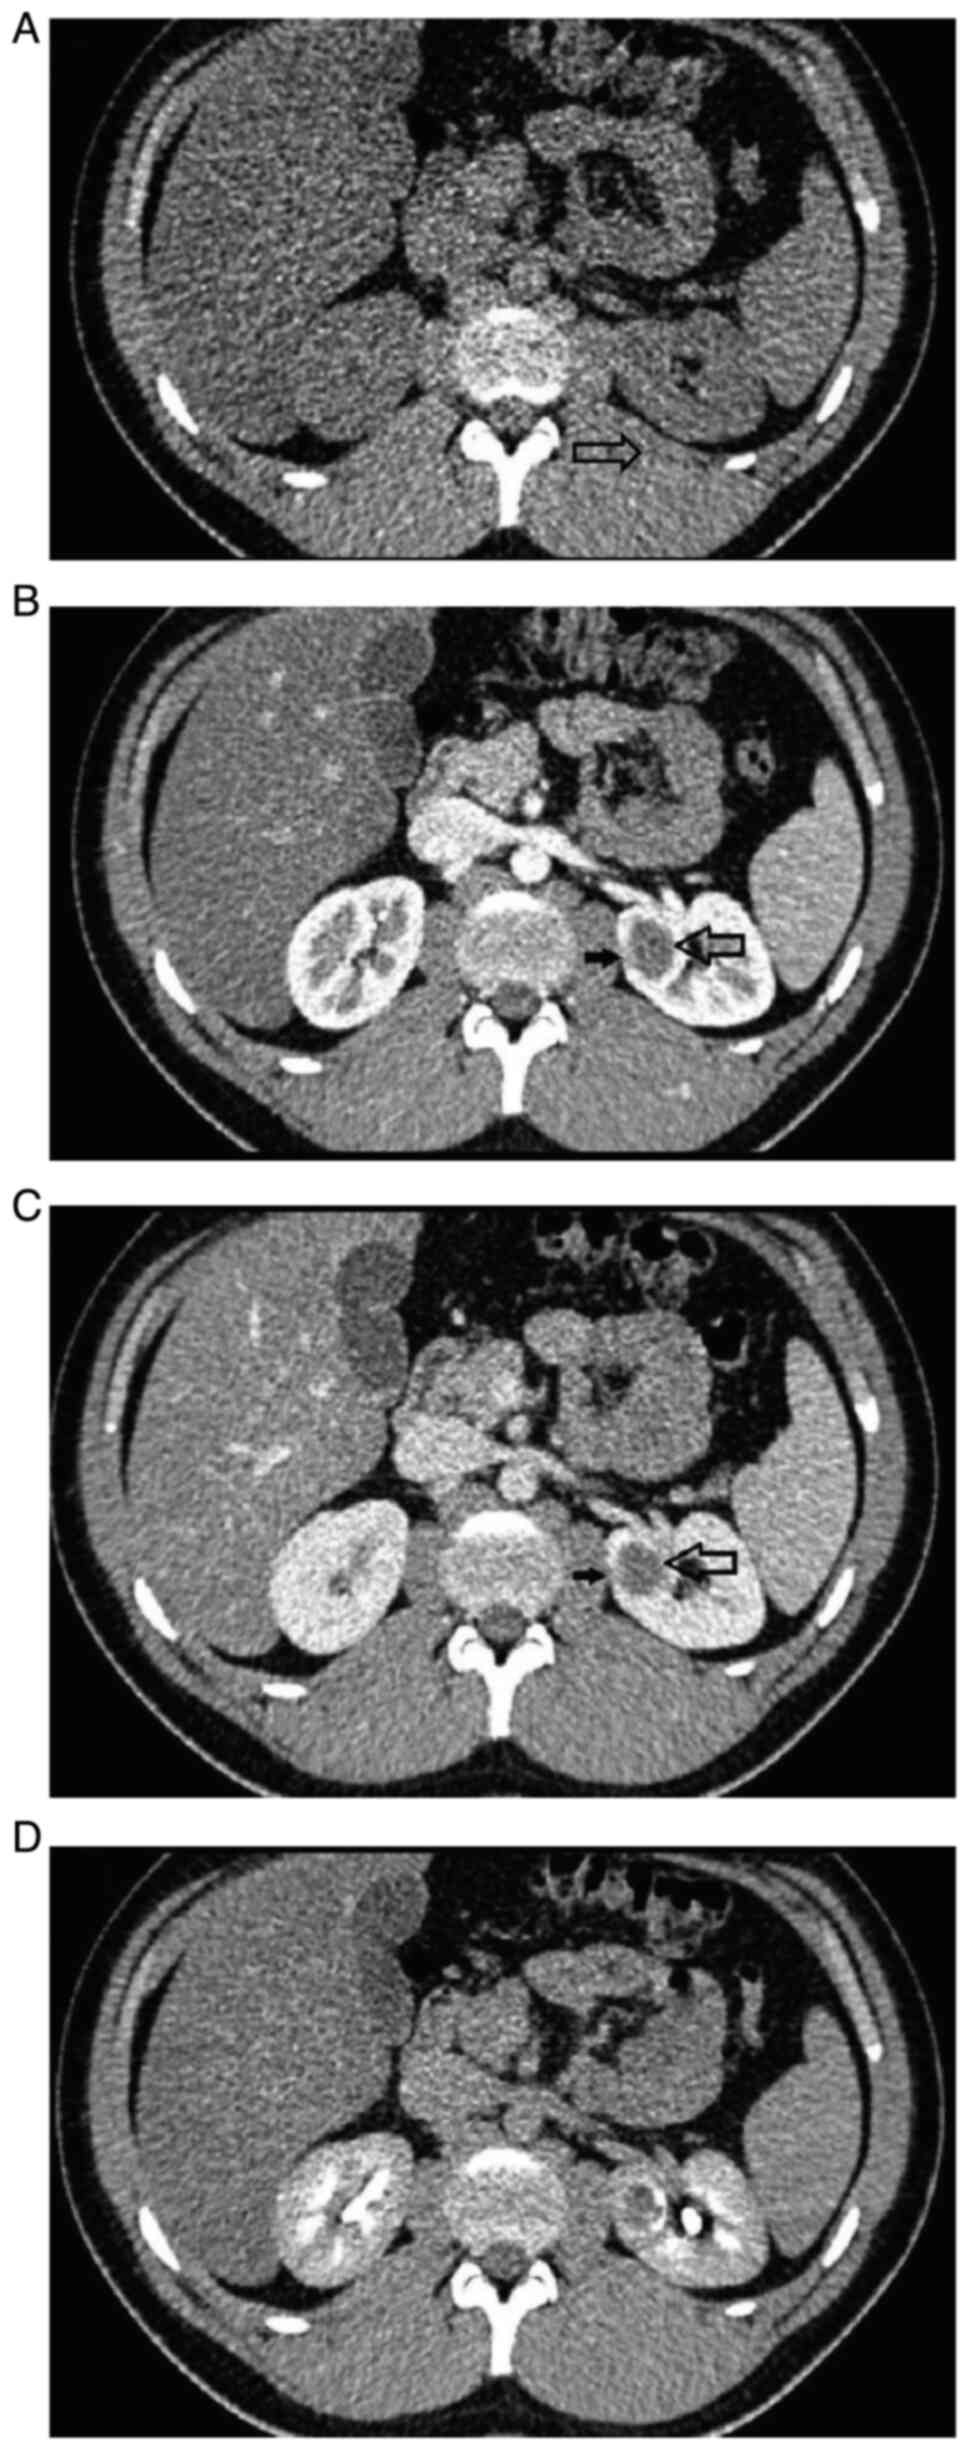

Mixed epithelial and stromal tumor of the kidney: A case report

Mixed epithelial and stromal tumor (MEST) is a rare neoplasm of the kidney, affecting mostly women at menopausal age. While few cases of malignant transformation have been described in the literature, MEST is usually considered a benign tumor with minimal risk of local recurrence or distance metastases. The current study presents a case of a 18‑year old male patient with a cystic tumor of the left kidney incidentally diagnosed on magnetic resonance imaging of the heart performed for other reasons. The patient underwent a partial nephrectomy, with perioperative course being uneventful. The pathology report revealed MEST of the kidney. No local recurrence nor disease progression have been observed in the patient during the one‑year follow‑up period. The present case report is evidence that may help in developing guidelines on the management of patients with benign renal masses.

Figure 1